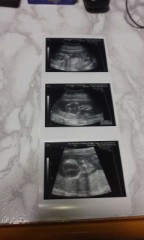

今日仕事終わってから、産婦人科行って来ました。\(^ω^)/

妊娠14週目で、お腹の赤ちゃんも順調に成長してました。(o^^o)♪

お腹の赤ちゃん写真です。(*^_^*)